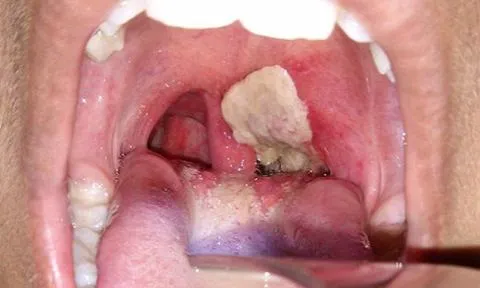

Dấu hiệu của bệnh bạch hầu là lớp giả mạc ở đường hô hấp trên.

BS Trần Đăng Khoa phân tích, khi xâm nhập vào cơ thể, vi khuẩn bạch hầu tạo ra sang thương chính là lớp giả mạc màu trắng xám hoặc trắng ngà ở đường hô hấp trên. Đây là lý do loại bệnh này có tên “bạch hầu”. Một số dòng vi khuẩn bạch hầu có thể tạo ra độc tố, khiến bệnh diễn tiến nặng, gây biến chứng viêm cơ tim, viêm đa dây thần kinh….